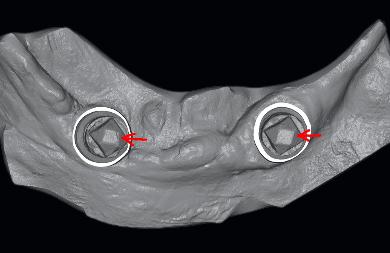

Des piliers de scannage ont été placées sur les implants en bouche et scannés avec le scanner iTero.

On a placé également sur les analogues d'implants des moulages définitifs et scanné ces modèles avec un scanner de laboratoire extra-oral (Lava ScanST). Deux modèles de conception en 3 dimensions assistée par ordinateur des piliers de scan avec axe prédéterminé ont été importés et enregistrés, avec chacun des équivalents numérisés.

La distance entre les centres de thetop des piliers de scan et l'angulation entre les piliers de scan a été évaluée. Ces valeurs ont été comparées avec les valeurs témoins.